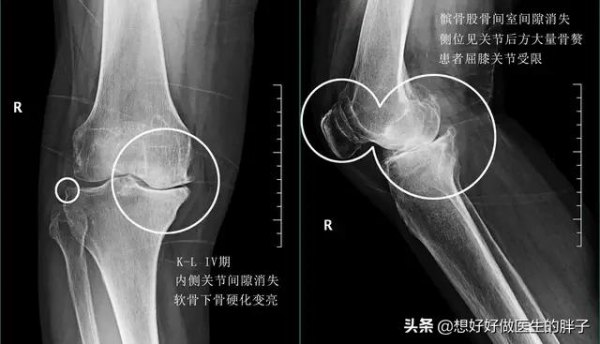

通常情况下,我们根据膝关节x线的表现中关节间隙是否狭窄,以及骨赘形成的程度将骨关节炎分为4期。

四期的骨关节炎患者关节间隙会有明显的狭窄,患者的关节功能也会出现明显的受限,出现这种情况,往往都是由于骨赘形成的量过大,阻挡了患者在屈伸过程当中的进程。